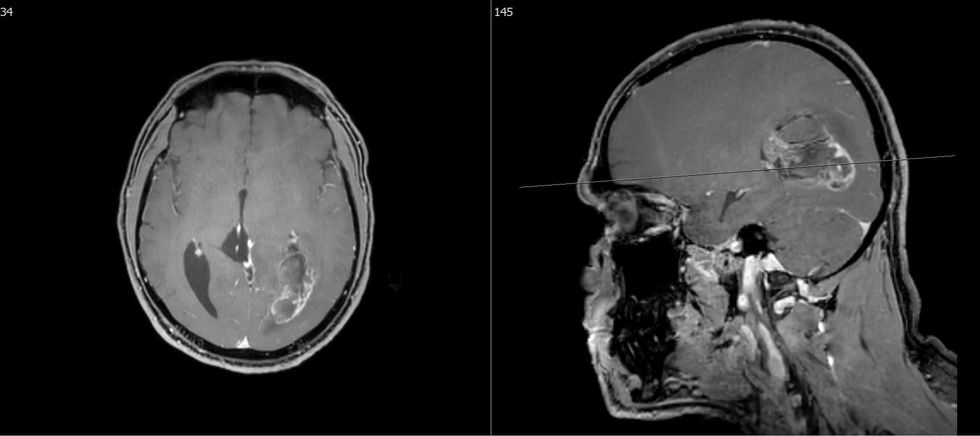

Metastazat e trurit ndodhin në 15-30% të pacientëve me kancer. Tumori primar është kryesisht kanceri i mushkërisë (44%), i gjirit (10%), i veshkës (7%), i traktit gastrointestinal (6%) dhe melanoma (3%).

Trajtimi i metastazave në tru është i mundur duke përdorur modalitete të ndryshme. Koncepti i trajtimit varet nga faktorë të ndryshëm, si lokalizimi, numri, simptomat e shkaktuara dhe gjendja e përgjithshme e pacientit si dhe situata e përgjithshme onkologjike. Në rastin e metastazave simptomatike, qëllimi i operacionit është përmirësimi i gjendjes për të mundësuar terapi të mëtejshme për pacientin edhe nëse ka disa metastaza.